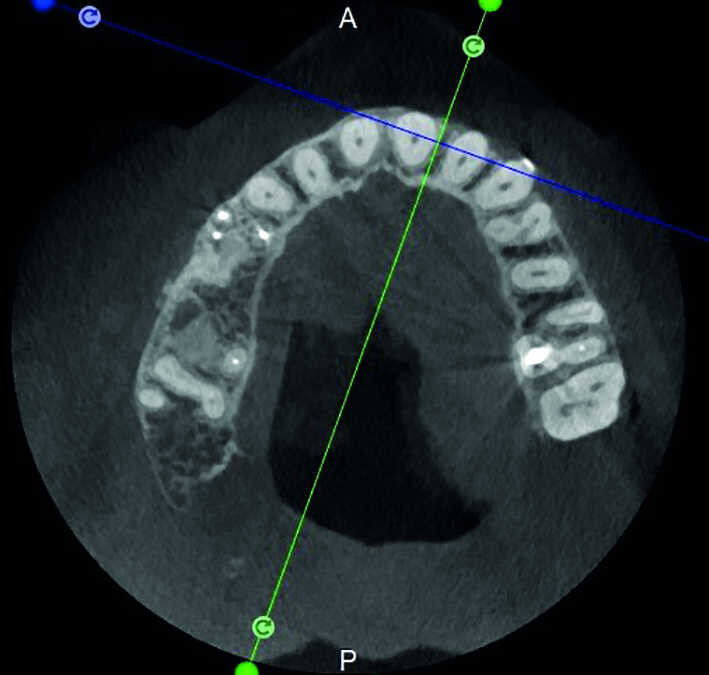

Le cas avec lequel je souhaite commencer mon exposé clinique est un exemple parfait de la difficulté à définir l’origine des symptômes d’un patient, par l’examen d’une simple radiographie intraorale. Non seulement l’examen 2D ne permet pas d’établir avec certitude la présence d’une lésion, mais surtout, il est impossible d’en déterminer la taille, la morphologie et le type. Au contraire, une analyse de l’imagerie 3D offre une image claire de la situation clinique. Chez ce patient, les coupes coronales et sagittales révèlent la présence d’une importante lésion s’étendant de l’apex de la racine mésiale de cette molaire jusqu’à la zone de furcation, tandis que les coupes axiales nous permettent d’analyser précisément l’anatomie endodontique et, en particulier, la forme de la racine mésiale, qui apparaît fusionnée avec la racine palatine. Un panorama complet du cas peut donc guider le processus de décision et orienter le plan de traitement vers une modalité bien précise de traitement (Figs. 1–4).